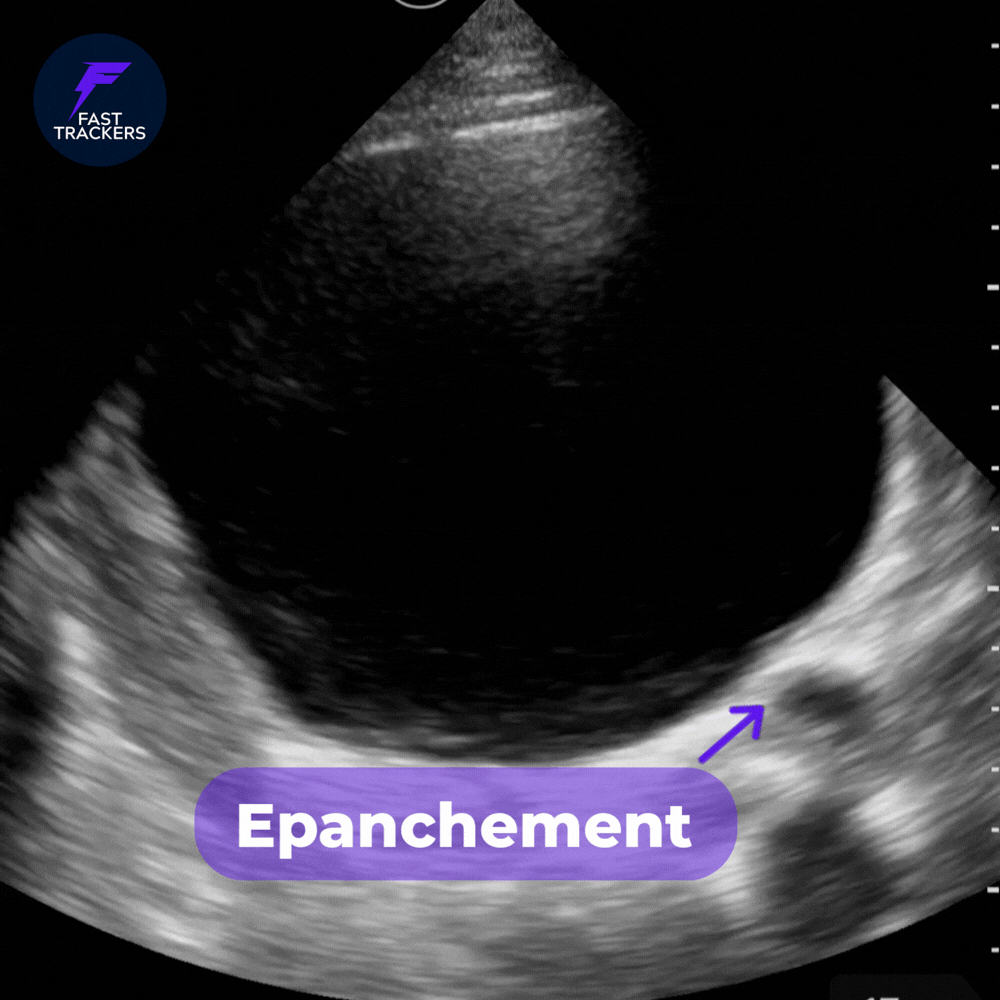

🔴 Liquide libre pelvien

• Collection anéchogène

• Située en arrière de la vessie

• Peut former une lame fine ou un volume plus important

Même une petite quantité peut être significative en contexte traumatique.

Noter la petite collection derrière la vessie.